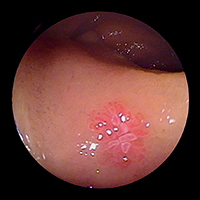

Немного по-другому выглядит ситуация с показаниями к капсульной эндоскопии при других патологиях тонкого кишечника — несомненна ее польза в диагностике различных полипозов (FAP-Syndrom (семейный наследственный полипоз), Peutz — Jaghers Syndrom) в первую очередь для планирования дальнейшей лечебной тактики и решения вопроса о необходимости хирургического вмешательства. Аналогичные показания касаются и пациентов с болезнью Крона, хотя в этом случае необходимо считаться с опасностью наличия стенозов и свищей — одного из наиболее частых ее осложнений, — являющихся прямым противопоказанием к капсульной эндоскопии. Для таких случаев была специально разработана Patency-Капсула, оболочка которой частично растворяется под влиянием кишечного содержимого — в результате к концу исследования она превращается в мешочек с соответствующим содержимым и может беспрепятственно преодолеть все стенозы и спайки. Насколько это, несомненно, оригинальное, но и не менее дорогостоящее решение найдет широкое признание в эндоскопической практике — вопрос времени. Достаточно шаткими являются и показания к капсульной эндоскопии в диагностике опухолей, и главным лимитирующим фактором здесь выступает уже упомянутая выше невозможность биопсии.

Первые результаты клинических исследований эффективности РРЕ выглядят весьма обнадеживающе — около 80% энтероскопий являются результативными. При этом в каждом втором случае было успешно проведено эндоскопическое лечение (лазерная коагуляция, дилатация стенозов или полип-

эктомия), а у каждого четвертого пациента это ис-

следование сыграло решающую роль в выборе дальнейшей медикаментозной тактики (как, например, при болезни Крона) или показаний к радикальному хирургическому лечению (при ее осложнениях).